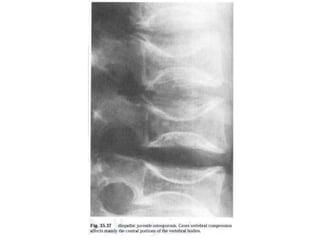

Idiopathic juvenile osteoporosis:

Patient typically presents before puberty (8-

13 years) and have osteoporosis (lumbar &

thoracic vertebrae) that is progressive initially

and later stabilizes.

Vertebral compression fracture and

characteristically metaphyseal fractures

specially of lower limb bones occur.